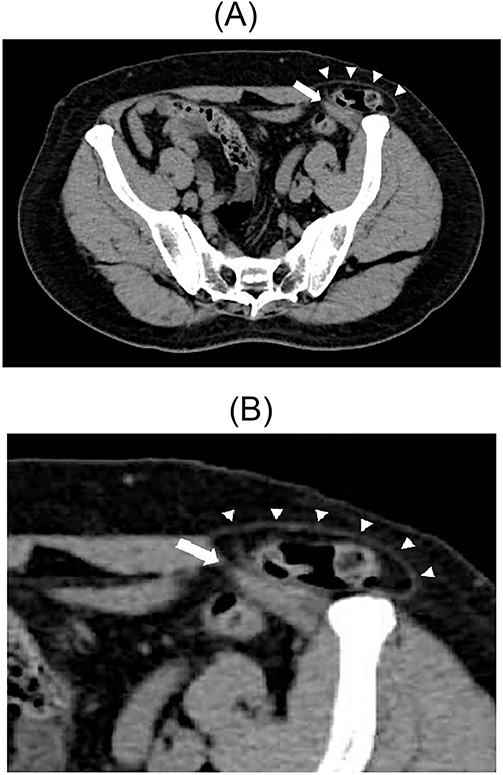

A 79-year-old male patient with a medical history of right inguinal hernia presented to the emergency department with right inguinal swelling and pain. We found the inguinal swelling, which extended toward the head, to be atypical. In addition, contrast-enhanced computed tomography (CT) scan revealed that a portion of the small intestine was incarcerated between the internal and external oblique muscles, and the hernia contents had prolapsed cranially from the hernial orifice. Furthermore, the sagittal view revealed that the contents of the hernia had prolapsed ventrally and not along the spermatic cord (Figs 1 and 2). Therefore, we diagnosed it as a right interparietal inguinal hernia, and laparoscopic hernia repair was planned. Owing to the fact that the manipulative reduction was difficult, we planned to release the incarceration first.

Contrast-enhanced CT scan; an incarcerated bowel was observed in the right inguinal region; the small bowel was incarcerated between internal and external oblique muscles; the white arrow indicates the internal oblique muscle, and the white triangles indicate the external oblique muscle.

Sagittal section of contrast-enhanced CT; the black triangles indicate the incarcerated small bowel.